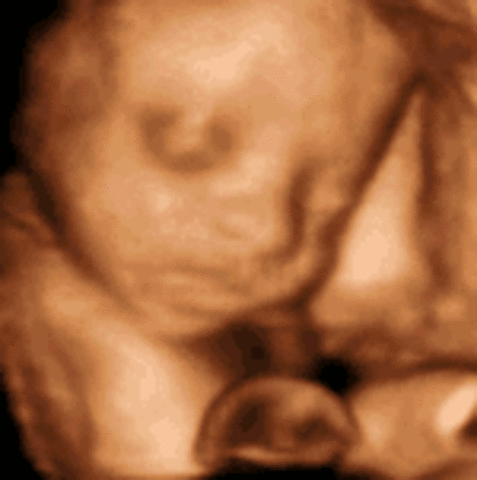

The baby is about 14 inches long and weighs over 1.7 pounds. At this time the baby's hands become quite active, and their eyes beguin to open.

The baby's brain continues to rapidly grow, and their eyes are able to open and close. At this time the baby weighs almost 2 pounds and is around 14.5 inches in size.

The baby's milk teeth have developed under their gums and the hair on their head is clearly seen. The baby has a regular schedulenow, for instance what times they are active or asleep.

The baby now wieghs abut 1150 gm. They are able to respond to pain and their muscles and lungs continue to mature. The baby is sensitive to light and begin to develop taste preferences.